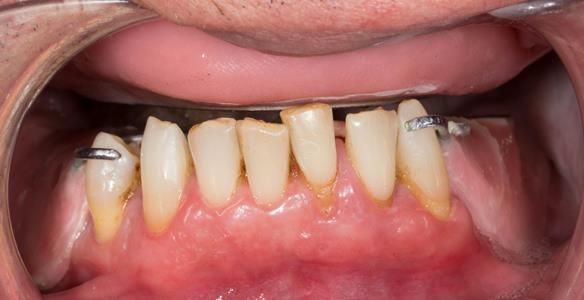

This newsletter describes in step by step detail the transition from acrylic based immediate dentures to metal based definitive dentures.

- Extraction of all upper teeth and LR5 and LL4 and fitting of immediate acrylic based (Mk 1) dentures - complete upper and lower partial

- Definitive dentures (Mk 2) – complete upper metal reinforced and lower cobalt chromium based partial of hygienic Scandinavian design to be made 9 - 12 months after extractions of all upper teeth and LR5 and LL4

The clinical situation and treatment process is shown in detail below with photographs.